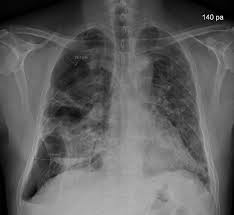

Bullous lung disease symptoms. There are several subtypes of emphysema including subcutaneous emphysema bullous. Group B GOLD 1 or 2. Most people with bullous emphysema experience shortness of breath wheezing coughing up phlegm and centralized pain in their chests especially when engaging in physical activity.

This emphysema also includes deterioration of alveolar tissue and this is basically lung tissue that makes up the walls between air sacs. Bullous Lung Disease is the most common form of emphysema. As the disease gets worse scars form and the tissue becomes stiff and thick.

Some patients suffer from nausea loss of appetite and fatigue as a. Patients frequently present with nonspecific symptoms including intermittent wheeze and cough and these are often attributed to other conditions such as asthma and smoking-related COPD especially when there is concurrent heavy smoking history. As the disease progresses you may find it increasingly difficult to breathe and engage in daily activity.

Emphysematous bullae can cause many respiratory problems including shortness of breath. Your FEV 1 is between 50 and 80. The harmful effects of tobacco smoking especially with regard to the aetiology of chronic obstructive pulmonary disease are well documented3 Large emphysematous bullae may develop usually in the context of significant tobacco exposure over many years and tend to be associated with airway obstruction reduced gas transfer factor and diffusion coefficient and evidence of centrilobular.

This is condition which is characterized by abnormal and enlarged air spaces within the lungs.